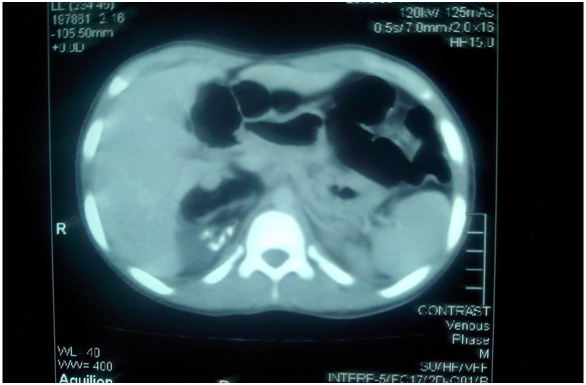

An 11years old boy, a known case of Down’s syndrome, presented with localized and intermittent pain in right lumbar region for one year. There was no history of fever, weight loss, burning micturition, hematuria or any previous surgical intervention. Patient was a product of consanguineous marriage. On examination, the abdomen was soft, non-tender, non-distended and with no palpable mass. The Ultrasound revealed a 4x3.5x5cm predominantly echogenic mass with calcification and cystic area in the right suprarenal region, compressing the right kidney inferiorly. All the baseline investigations were unremarkable. Echocardiography showed dysplastic pulmonary valve with mild pulmonary stenosis. Alpha feto protein was 0.654IU/ml (reference range<5.0). The child was also found to be having positive Hepatitis C status. Computed Tomography (CT) scan was obtained which showed a suprarenal mass (Figure 1-2). The patient was discussed in tumor board and was shifted to the department of pediatric surgery with the suspicion of right adrenal teratoma. Patient was optimized and surgery was planned. The tumor was surgically excised, yielding a 7x5x5cm grey colored mass. Grossly, it appeared cystic with clear serous fluid oozing out on cutting. On microscopic examination it was a cyst without any lining, lumen having hemorrhage along with scattered hemosiderin laden macrophages. Wall of the cyst revealed sheaths of hemosiderin laden macrophages with underlying lymphoid tissue, scattered smooth muscle bundles and foci of adipose tissue. There was focal calcification and a single focus of cartilage along with skeletal muscle and nerve bundles, so diagnosis of Adrenal Teratoma was made. The post-operative period was uneventful and patient is doing well to date after a follow up of 2 years.

Figure 1 Showing CT image of abdomen.